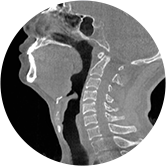

颈椎

气道